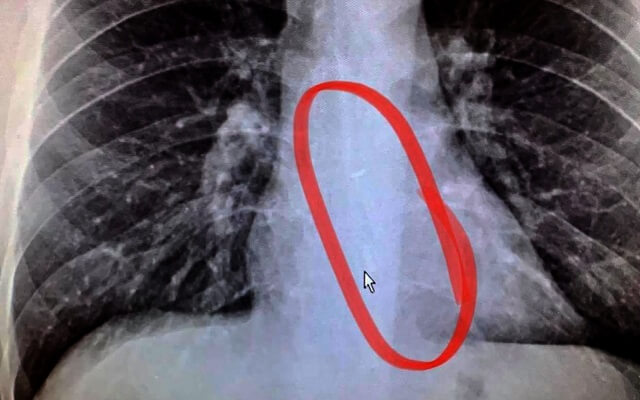

يمكنك أن تتخيل أين استمرت القصة ، في غرفة بالمستشفى للحصول على صورة بالأشعة السينية لـ Gauthier. الصورة تتحدث عن نفسها.

في الواقع ، كان برادفورد قد ابتلع إحدى سماعات AirPods الخاصة به أثناء نومه واستقرت في الجزء السفلي من مريئه. لإزالتها ، كان على الأطباء إجراء تنظير داخلي طارئ.